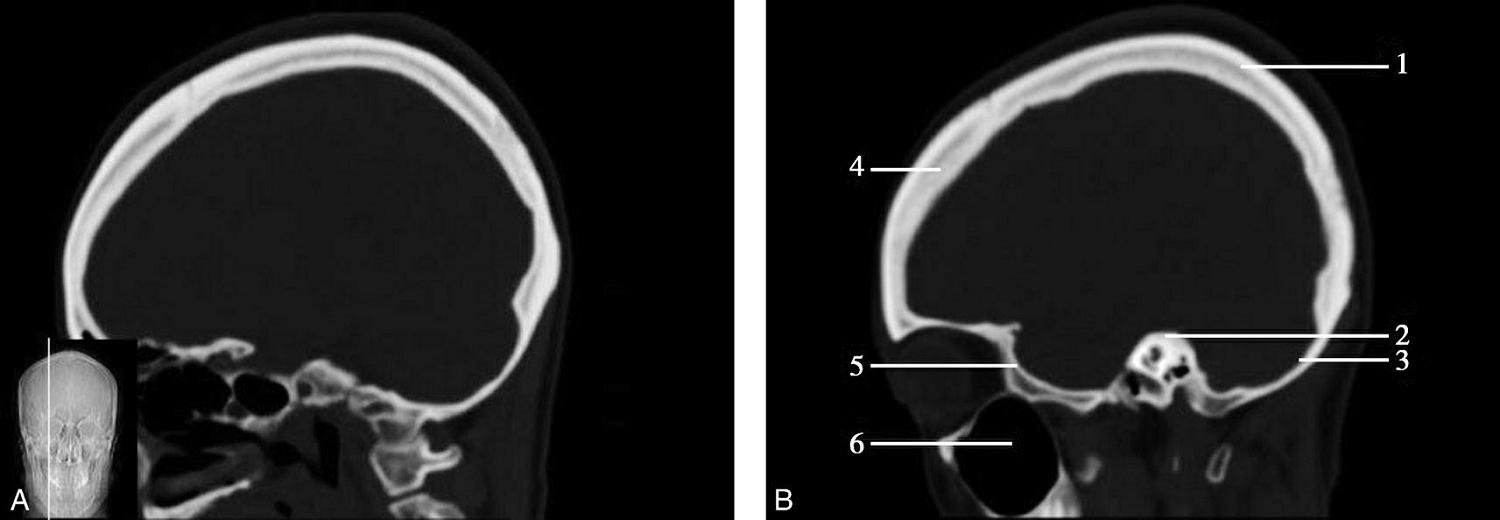

图1-2-2 颅底层面(骨窗)

A.横断面;B.横断面标注

1.鼻骨;2.筛窦纸板;3.颧骨眶突;4.翼腭窝;5.蝶骨大翼;6.卵圆孔;7.破裂孔;8.颞骨颧突;9.棘孔;10.斜坡;11.颞骨岩部;12.乳突;13.颈静脉孔;14.枕乳突缝;15.枕骨;16.枕内隆凸